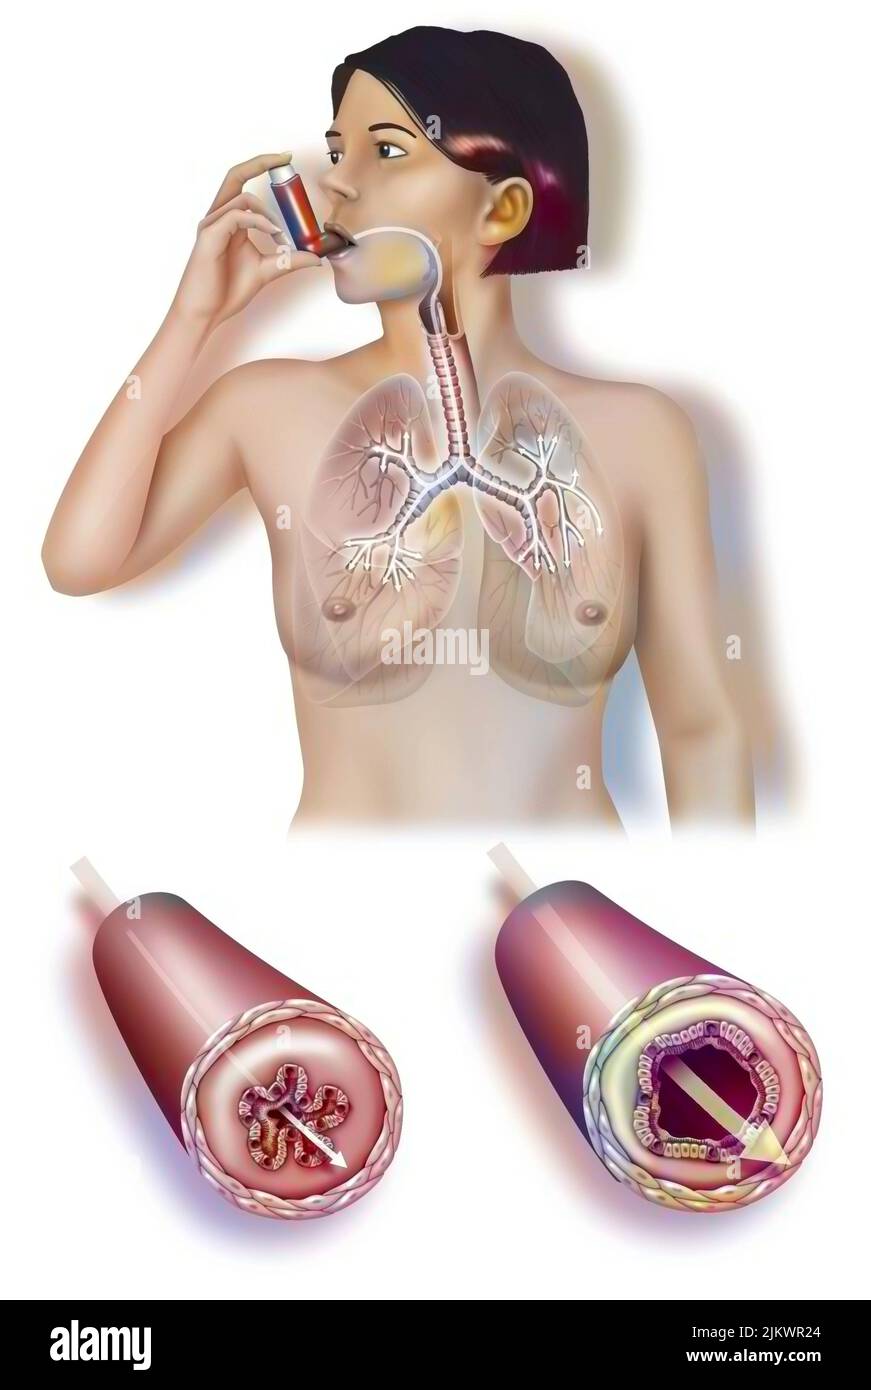

RF2JKWR24–Femme prenant un inhalateur pour soulager une crise d'asthme avec un tube bronchique pendant et après l'attaque.